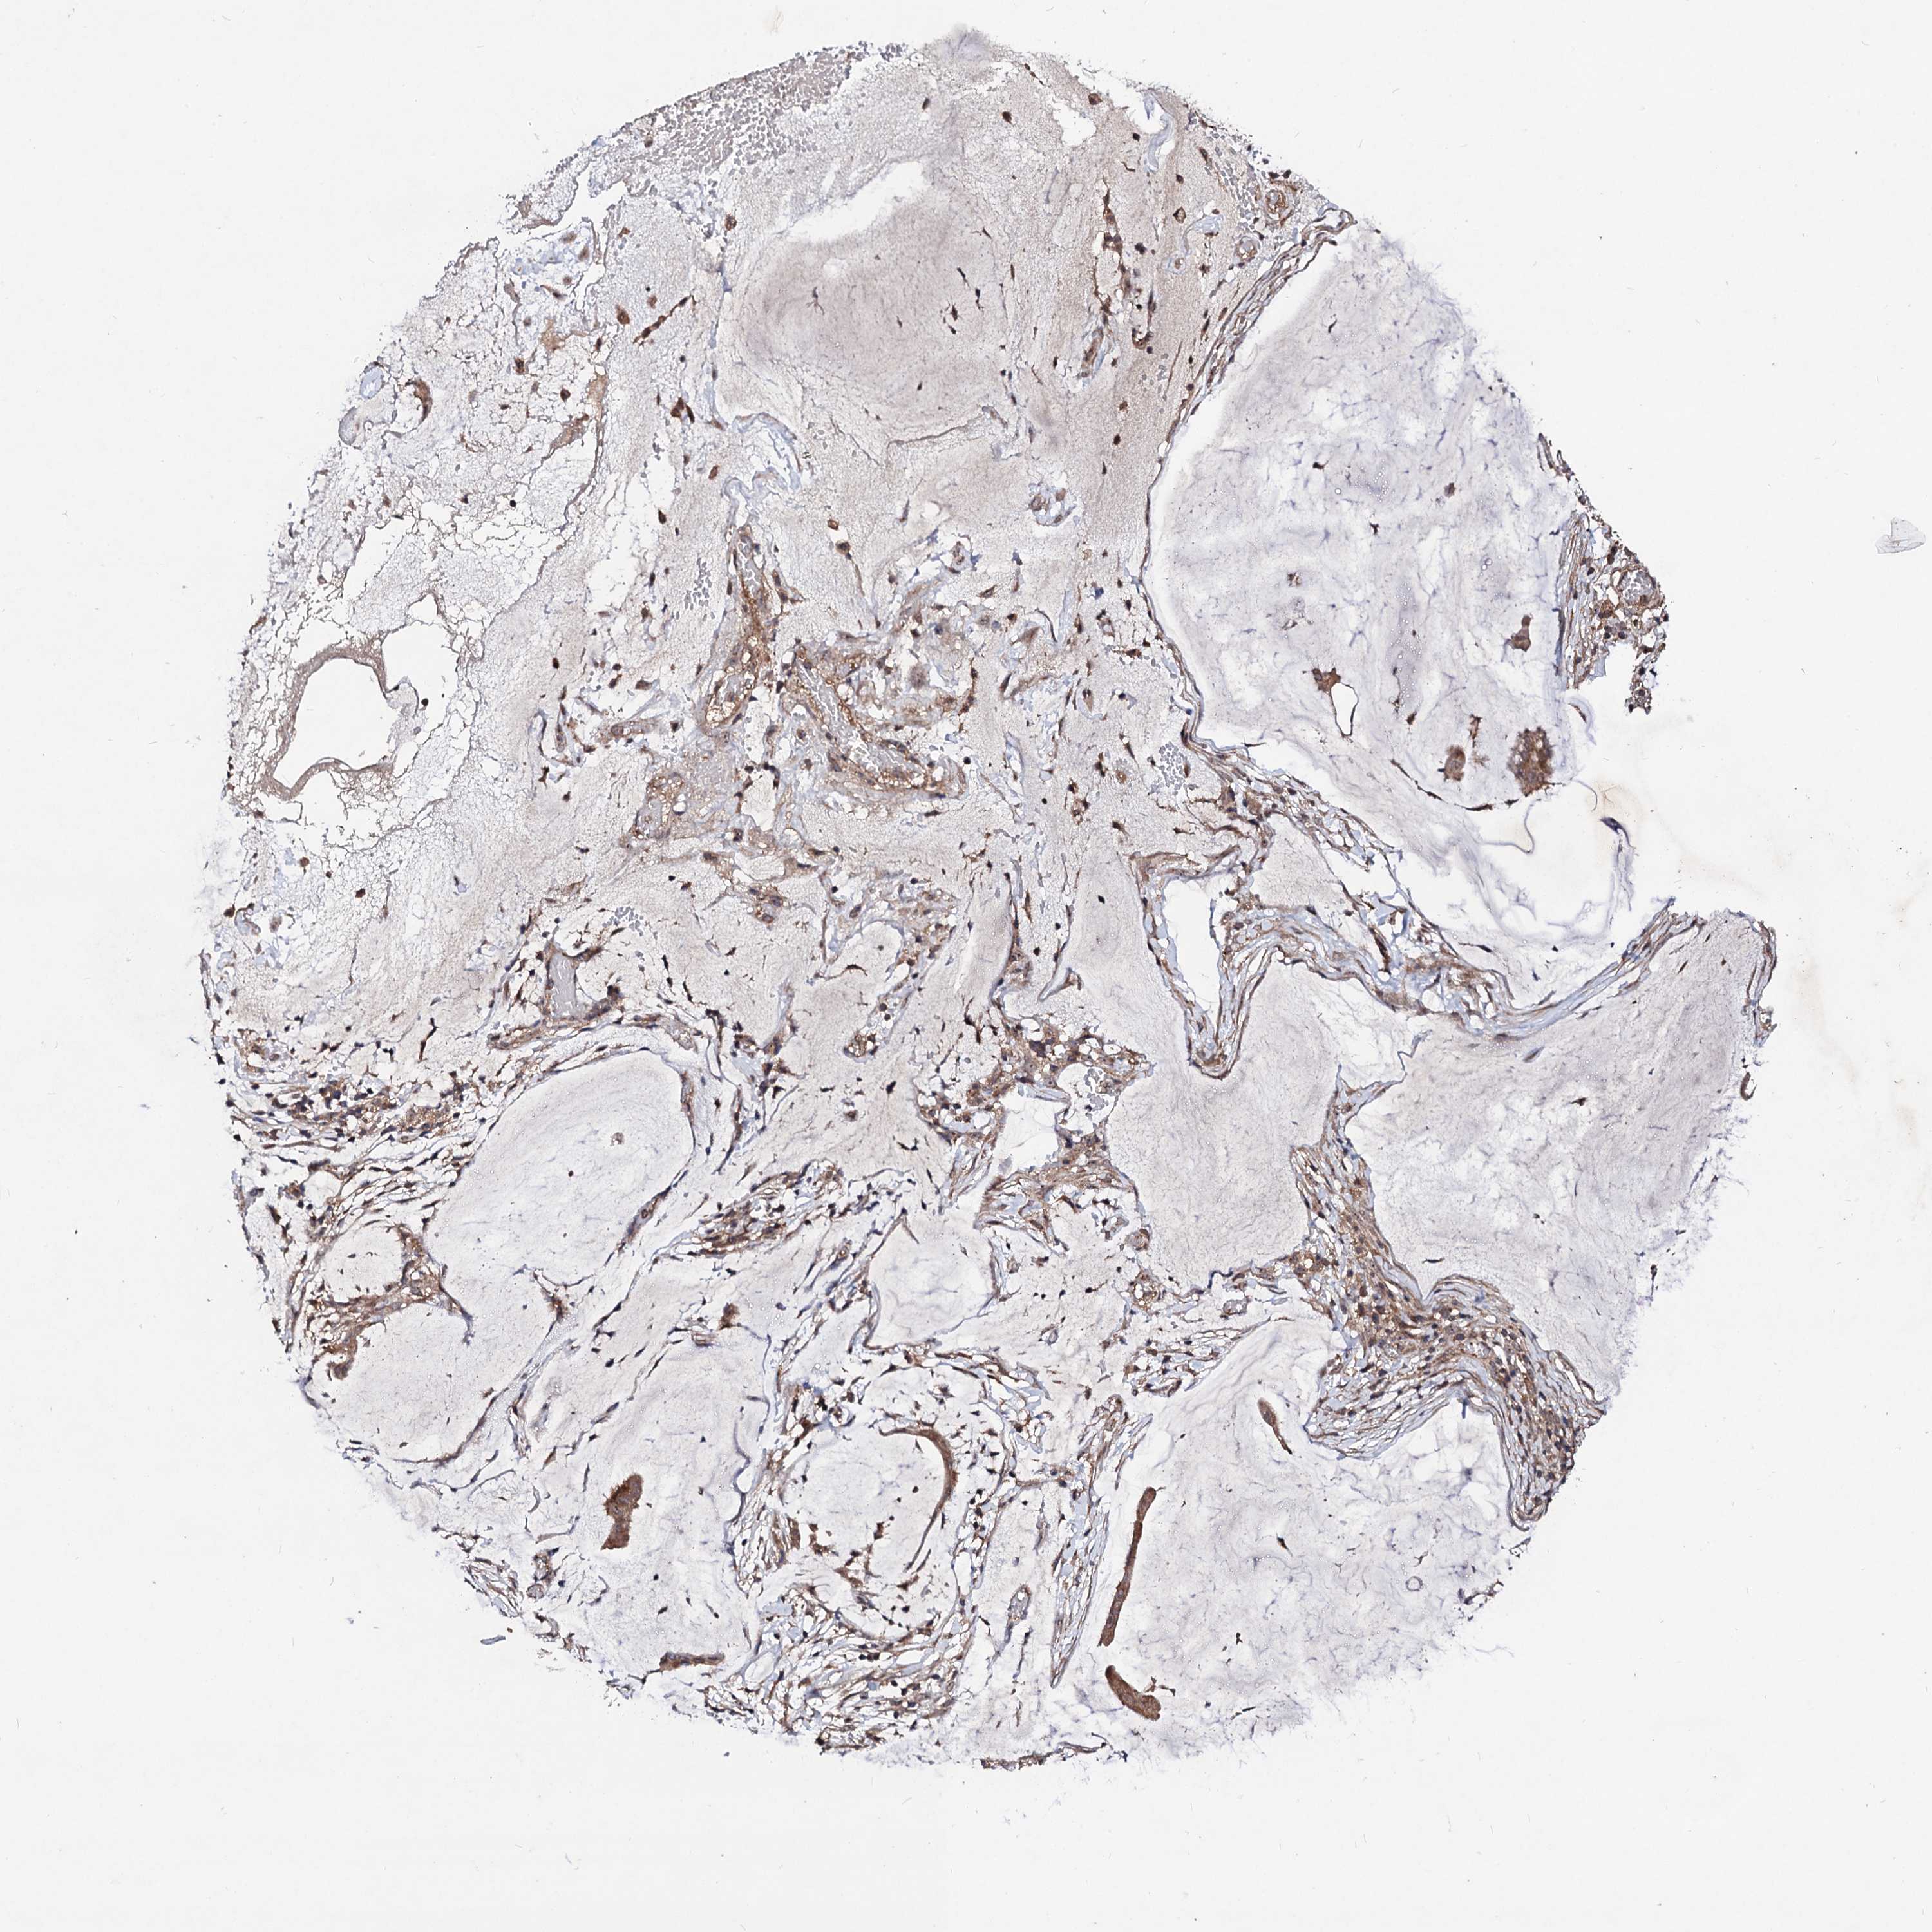

OVARIAN CANCER - Protein expressioni

A mouse-over function shows sample information and annotation data. Click on an image to view it in a full screen mode. Samples can be filtered based on level of antibody staining by selecting one or several of the following categories: high, medium, low and not detected. The assay and annotation is described here.

Note that samples used for immunohistochemistry by the Human Protein Atlas do not correspond to samples in the TCGA dataset.

Antibody stainingi

Antibody staining in the annotated cell types in the current human tissue is reported as not detected, low, medium, or high, based on conventional immunohistochemistry profiling in selected tissues. This score is based on the combination of the staining intensity and fraction of stained cells.

Each image is clickable and will lead to virtual microscopy that enables deeper exploration of all samples and also displays staining intensity scores, fraction scores and subcellular localization as well as patient and tissue information for each sample.

Antibody HPA041507

Antibody HPA041599

Cystadenocarcinoma, serous, NOS

Carcinoma, endometroid

Cystadenocarcinoma, mucinous, NOS

Carcinoma, NOS